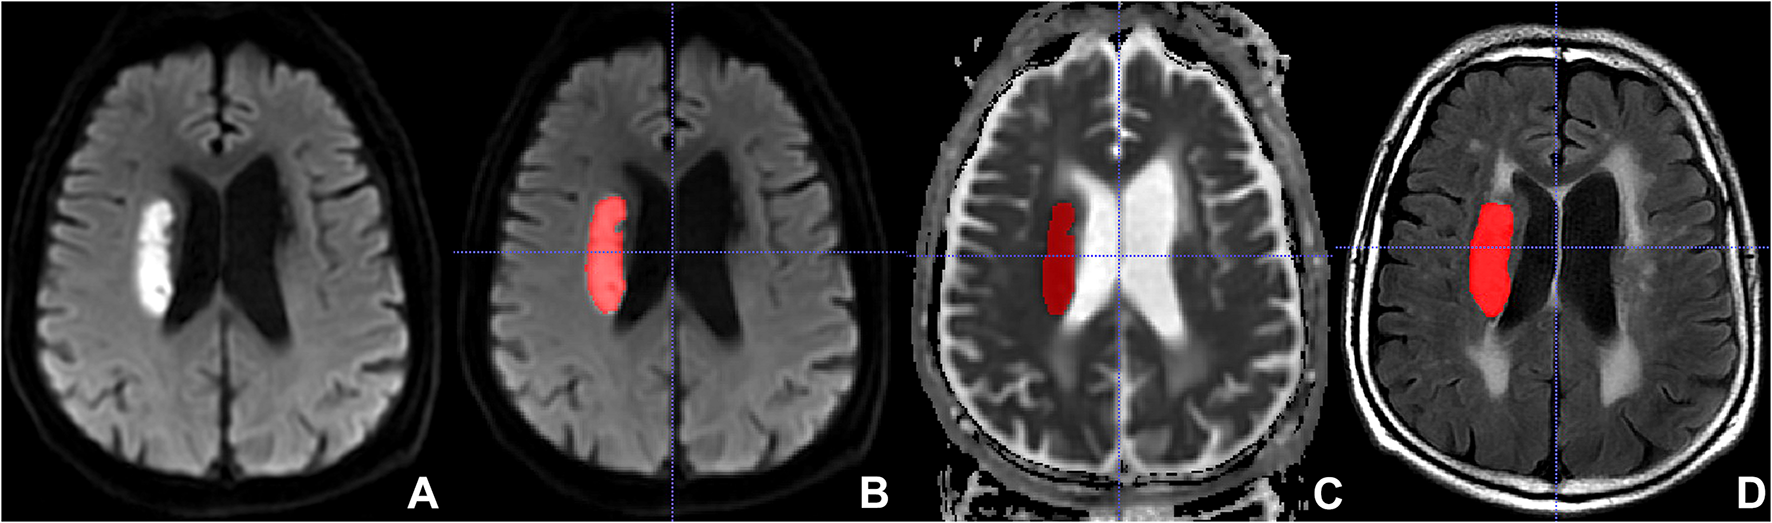

The FLAIR and ADC images of all eligible AIS patients were imported into the software Insight Segmentation and Registration Toolkit-ANAP (ITK-SNAP, version 3.8.01). Two neuroradiologists manually delineated the lesions on the ADC, then the region of interest (ROI) on ADC was copied to the corresponding FLAIR slice by using a free available software2 (Figure 2). In the areas of infarction, the FLAIR and ADC images were consequently segmented and were loaded into the open-source platform, PyRadiomics3, to extract radiomics features (van Griethuysen et al., 2017). Logistic regression analysis was employed for further selection of significant features. These selected significant features were used to calculate radscore.

FIGURE 2

Lesion segmentation with the Insight Segmentation and Registration Toolkit-ANAP (ITK-SNAP). (A) Non-segmented diffusion-weighted imaging (DWI). (B) Segmented DWI. (C) Segmented apparent diffusion coefficient (ADC). (D) Segmented fluid-attenuated inversion recovery (FLAIR).